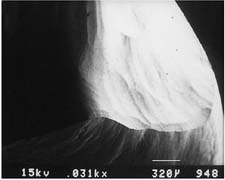

Considerable heat is generated by friction between a rotary instrument and the surface being prepared (Fig. 7-5). Excessive pressure, higher rotational speeds, and the type, shape, and condition of the cutting instrument (Fig. 7-6) may all increase generated heat.6 With a high-speed handpiece, a feather-light touch allows efficient removal of tooth material with minimal heat generation. Nevertheless, even with the lightest touch, the tooth overheats unless a water spray is used. This must be accurately directed at the area of contact between tooth and bur. The spray also removes debris—which is important because clogging reduces cutting efficiency (Fig. 7-7)—and prevents desiccation of the dentin (a cause of severe pulpal irritation).2,7 Debris accumulation has been shown to vary with rotary instrument shape. Shoulder- and chamfer-shaped diamonds may accumulate less debris. Debris is not readily removed after 5 minutes of ultrasonic cleaning.8

Fig. 7-6 Scanning electron micrographs of a rotary instrument. A, Unused diamond. B, Unused carbide. C, Worn diamond. D, Diamond particles have fractured at the level of the binder.

(Courtesy of Dr. J. L. Sandrik.)